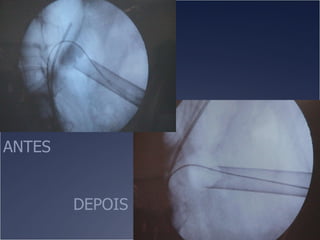

O documento discute o tratamento de urolitíase, especificamente a remoção de cálculos renais através de nefrolitotripsia. A cirurgia aberta é agora muito restrita devido aos avanços da ESWL e procedimentos endourológicos menos invasivos como ureteroscopia e cirurgia percutânea. A cirurgia laparoscópica está substituindo a cirurgia aberta como técnica menos invasiva que combina a tecnologia endourológica com a laparoscópica preservando